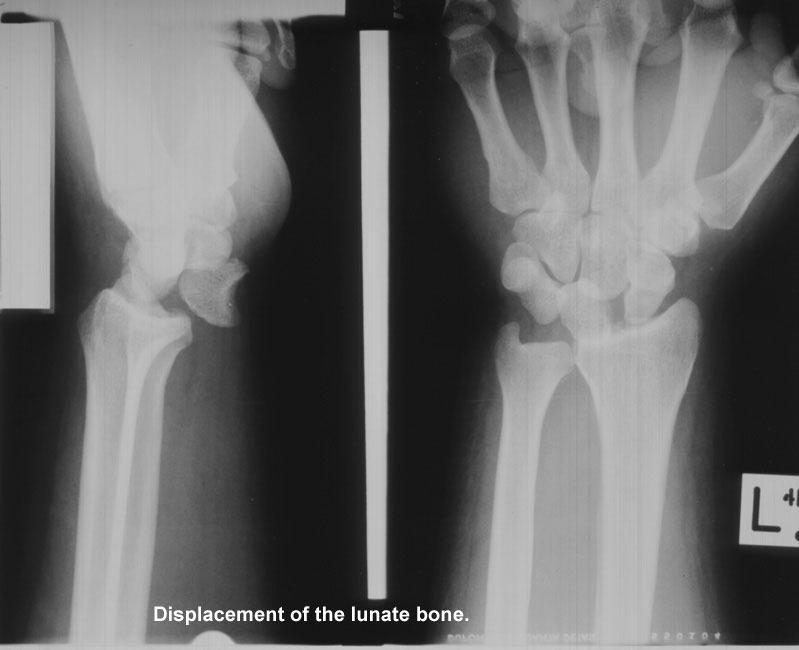

Other injuries that can occur following a fall on outstretched hands include dislocation of the lunate bone, posterior displacement of the distal radial epiphysis (in children), fracture of the clavicle (in adolescents), and fracture of the distal radius (Colles' fracture--usually in older adults).